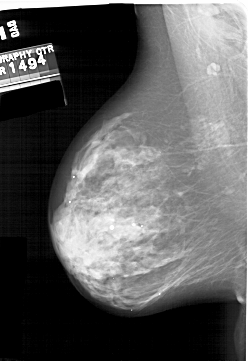

A_2000_1.LEFT_MLO

LEFT_MLO LINES 6121 PIXELS_PER_LINE 4216 BITS_PER_PIXEL 12 RESOLUTION 43.5 NON_OVERLAY